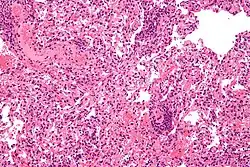

Lung transplant rejection

Deontological issues are issues about whether a person has an ethical duty or responsibility to take an action. Nearly all scholars and societies around the world agree that voluntarily donating organs to sick people is ethically permissible. Although nearly all scholars encourage organ donation, fewer scholars believe that all people are ethically required to donate their organs after death. Similarly, nearly all religions support voluntary organ donation as a charitable act of great benefit to the community. Certain small faiths such as Jehovah's Witnesses and Shinto are opposed to organ donation based upon religious teachings; for Jehovah's Witnesses, this opposition is absolute whereas there exists increasing flexibility among Shinto scholars. Romani people are also often opposed to organ donation based on prevailing spiritual beliefs and not religious views per se.[149] Issues surrounding patient autonomy, living wills, and guardianship make it nearly impossible for involuntary organ donation to occur.